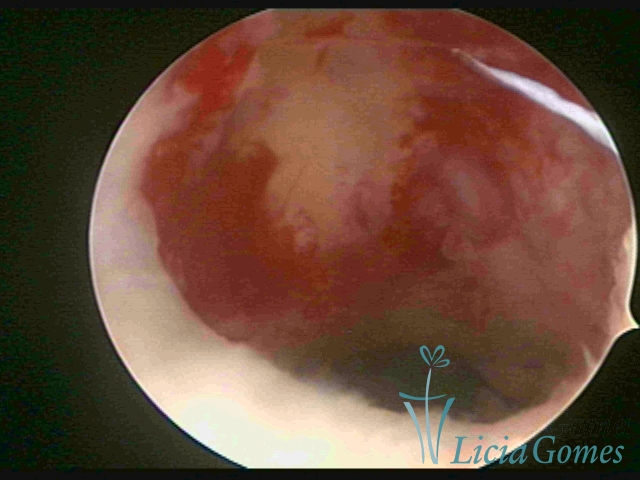

Retração da cicatriz de cesárea com fio não absorvível há 30 anos visão panorâmica